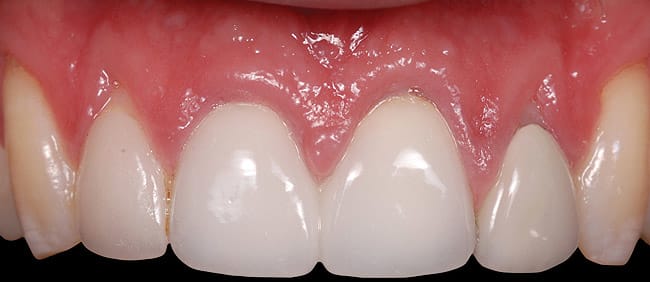

This case involved an ankylosed left central incisor. The patient’s chief complaint was that the incisor was dark and discolored (Figure 9 and Figure 10). Several possibilities were considered, including retaining the tooth or replacing it with an implant. The issue with retaining the incisor concerned the large pulpal canal and the need to aggressively prepare the tooth for a crown in order to mask the dark unesthetic dentin. Another concern was the long-term probability of external root resorption since it was ankylosed. The decision was made to extract and place an implant. The patient had good bone and good soft-tissue positions. The treatment plan was to extract and place the implant with an immediate protocol. The use of an immediate provisional was also considered, but the patient’s deep overbite and his desire to not have to be protective of the implant made the case for doing a bonded provisional. The incision design was done to allow for a facial flap but preserve the papilla. The extraction of the ankylosed incisor required magnification to dissect the tooth from the bone. The implant was placed and the site was grafted with hard and soft tissue. Figure 11 shows the implant, custom healing abutment, CTG, and closure with 7.0 vicryl sutures.

The final soft-tissue form was transferred with the impression by fabricating a custom impression coping, which was made with flowable composite and mimicked the cervical portion of the provisional restoration (Figure 12). The final restoration achieved the patient’s goal of matching the color and esthetic contours with the adjacent teeth. The gingival esthetics were ideal, making the implant undetectable from the natural dentition (Figure 13).